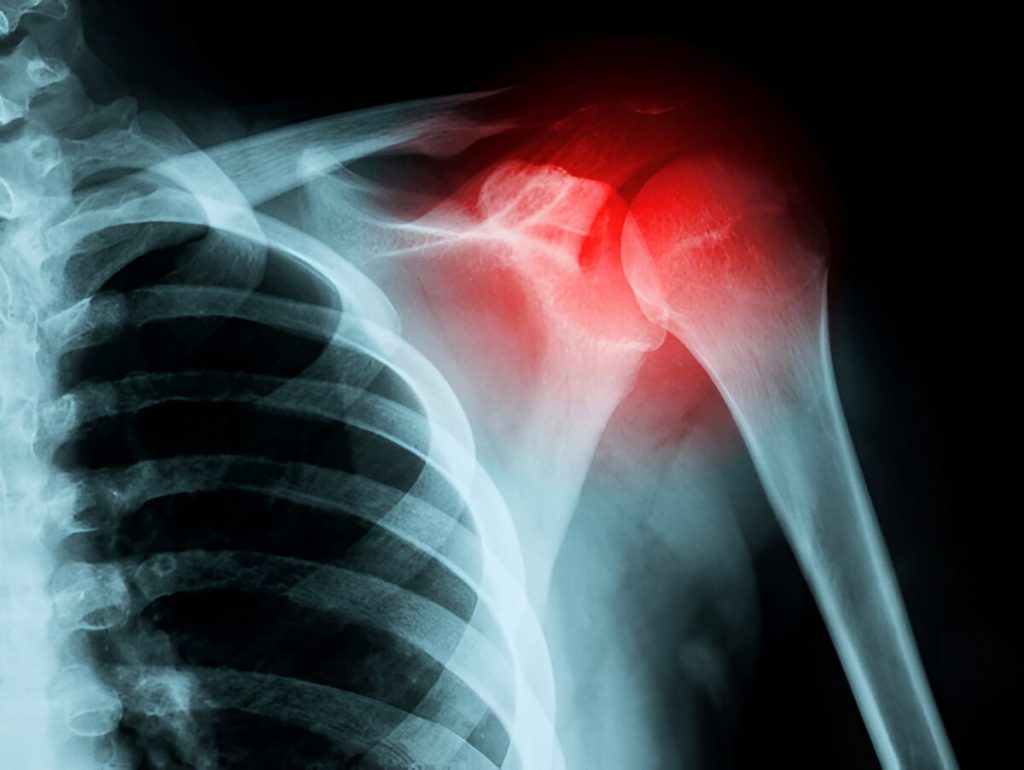

Glenohumeral joint – Ball-and-socket joint between humerus and scapula

Acromioclavicular (AC) joint – Between the clavicle and the scapula’s acromion

Osteoarthritis